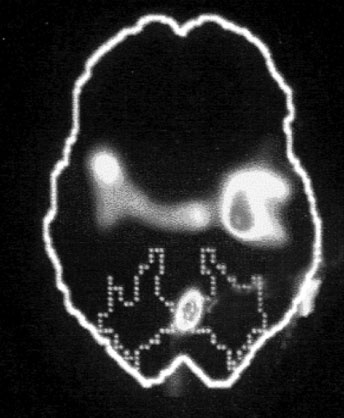

В. Зона Брока

Иллюстрация к книге — Тело помнит все [i_004.jpg]

Изображение мозга в процессе переживания травмы. Светлые пятна в лимбической коре (А) и зрительной коре (Б) соответствуют повышенной активности мозга в этих участках. На снимке (В) видна значительно пониженная активность речевого центра мозга.

Больше всего из полученных нами результатов нас поразила белая точка в левой фронтальной доле коры, так называемой зоне Брока. В данном случае изменение цвета означает значительный спад активности в этой области мозга.

Зона Брока – это один из речевых центров мозга, который зачастую бывает затронут у людей, перенесших инсульт, когда этот участок оказывается отрезан от кровотока. Без нормально функционирующей зоны Брока человек неспособен выражать словами свои мысли и чувства. Наши снимки показали, что при активации болезненных воспоминаний зона Брока отключалась.

Другими словами, перед нами было наглядное доказательство того, что последствия психологической травмы могут совпадать с последствиями физических повреждений, таких как инсульты, либо иметь с ними что-то общее.